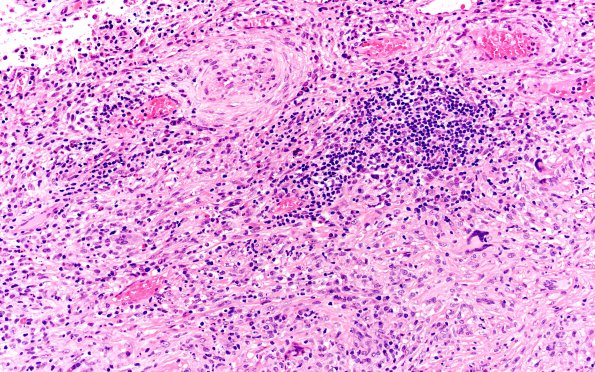

Washington University Experience | MISCELLANEOUS | Idiopathic Hypertrophic Pachymeningitis (IgG4 Disease) | 7B2 IgG4 disease (Case 7) H&E 20X 3

7B2,3 The inflammation is focal consisting of a heterogenous infiltrate including lymphocytes, plasma cells and histiocytes with focal granuloma formation containing multinucleated giant cells, scattered eosinophils and neutrophils. There is significant fibrosis and thickening of the walls of numerous vessels, likely following vasculitis. (H&E)